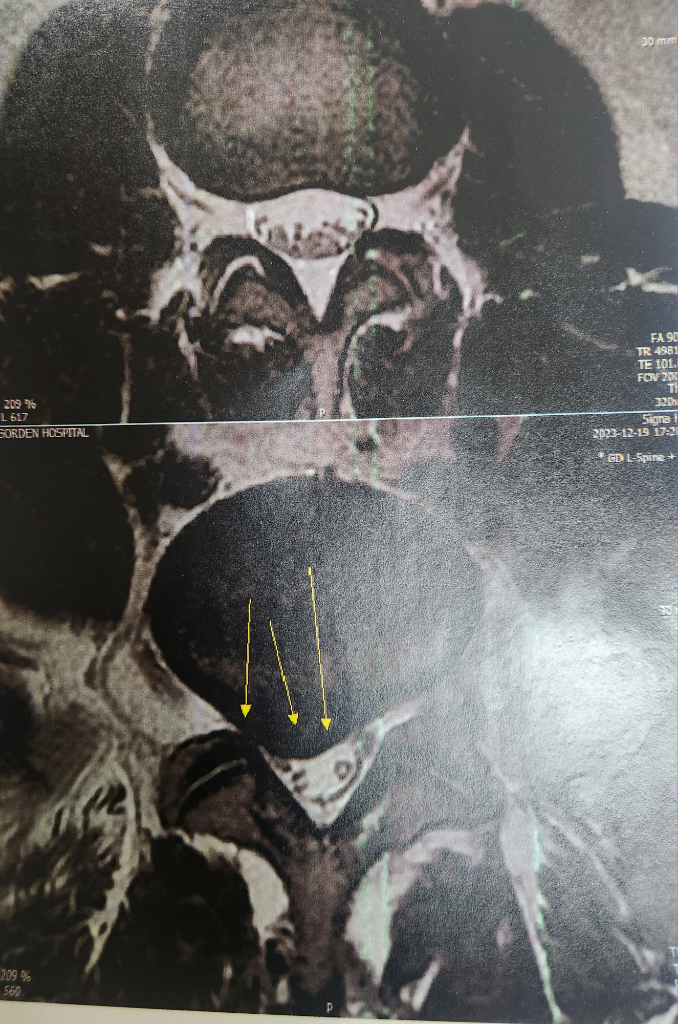

오른쪽 엉치부터 허벅지통증도 심하고 저림증세도 있어서 정형외과가서 신경주사3번정도..체외충격파4번정도 도수차료3번..호전이 돠지않아 mri찍었는데 수술해야된다고 병원아랑교수님 소개를 해주더라구요..다음날 다른한방병원가니까 한양이랑 약침맞으라하고...또다른 병원가니 거기서도 수술을 권하고..

탈출증이 심한 상황이긴 합니다. 한방병원이야 당연히 보존적 치료밖에 이야기할수 없으니 그런 것이고, 수술이 정 부담스러우시면 다리에 힘빠지는 증상이나 대소변을 보지 못하는 증상과 같은 응급상황에 주의하면서 통증을 참고 지내보실수는 있겠습니다.